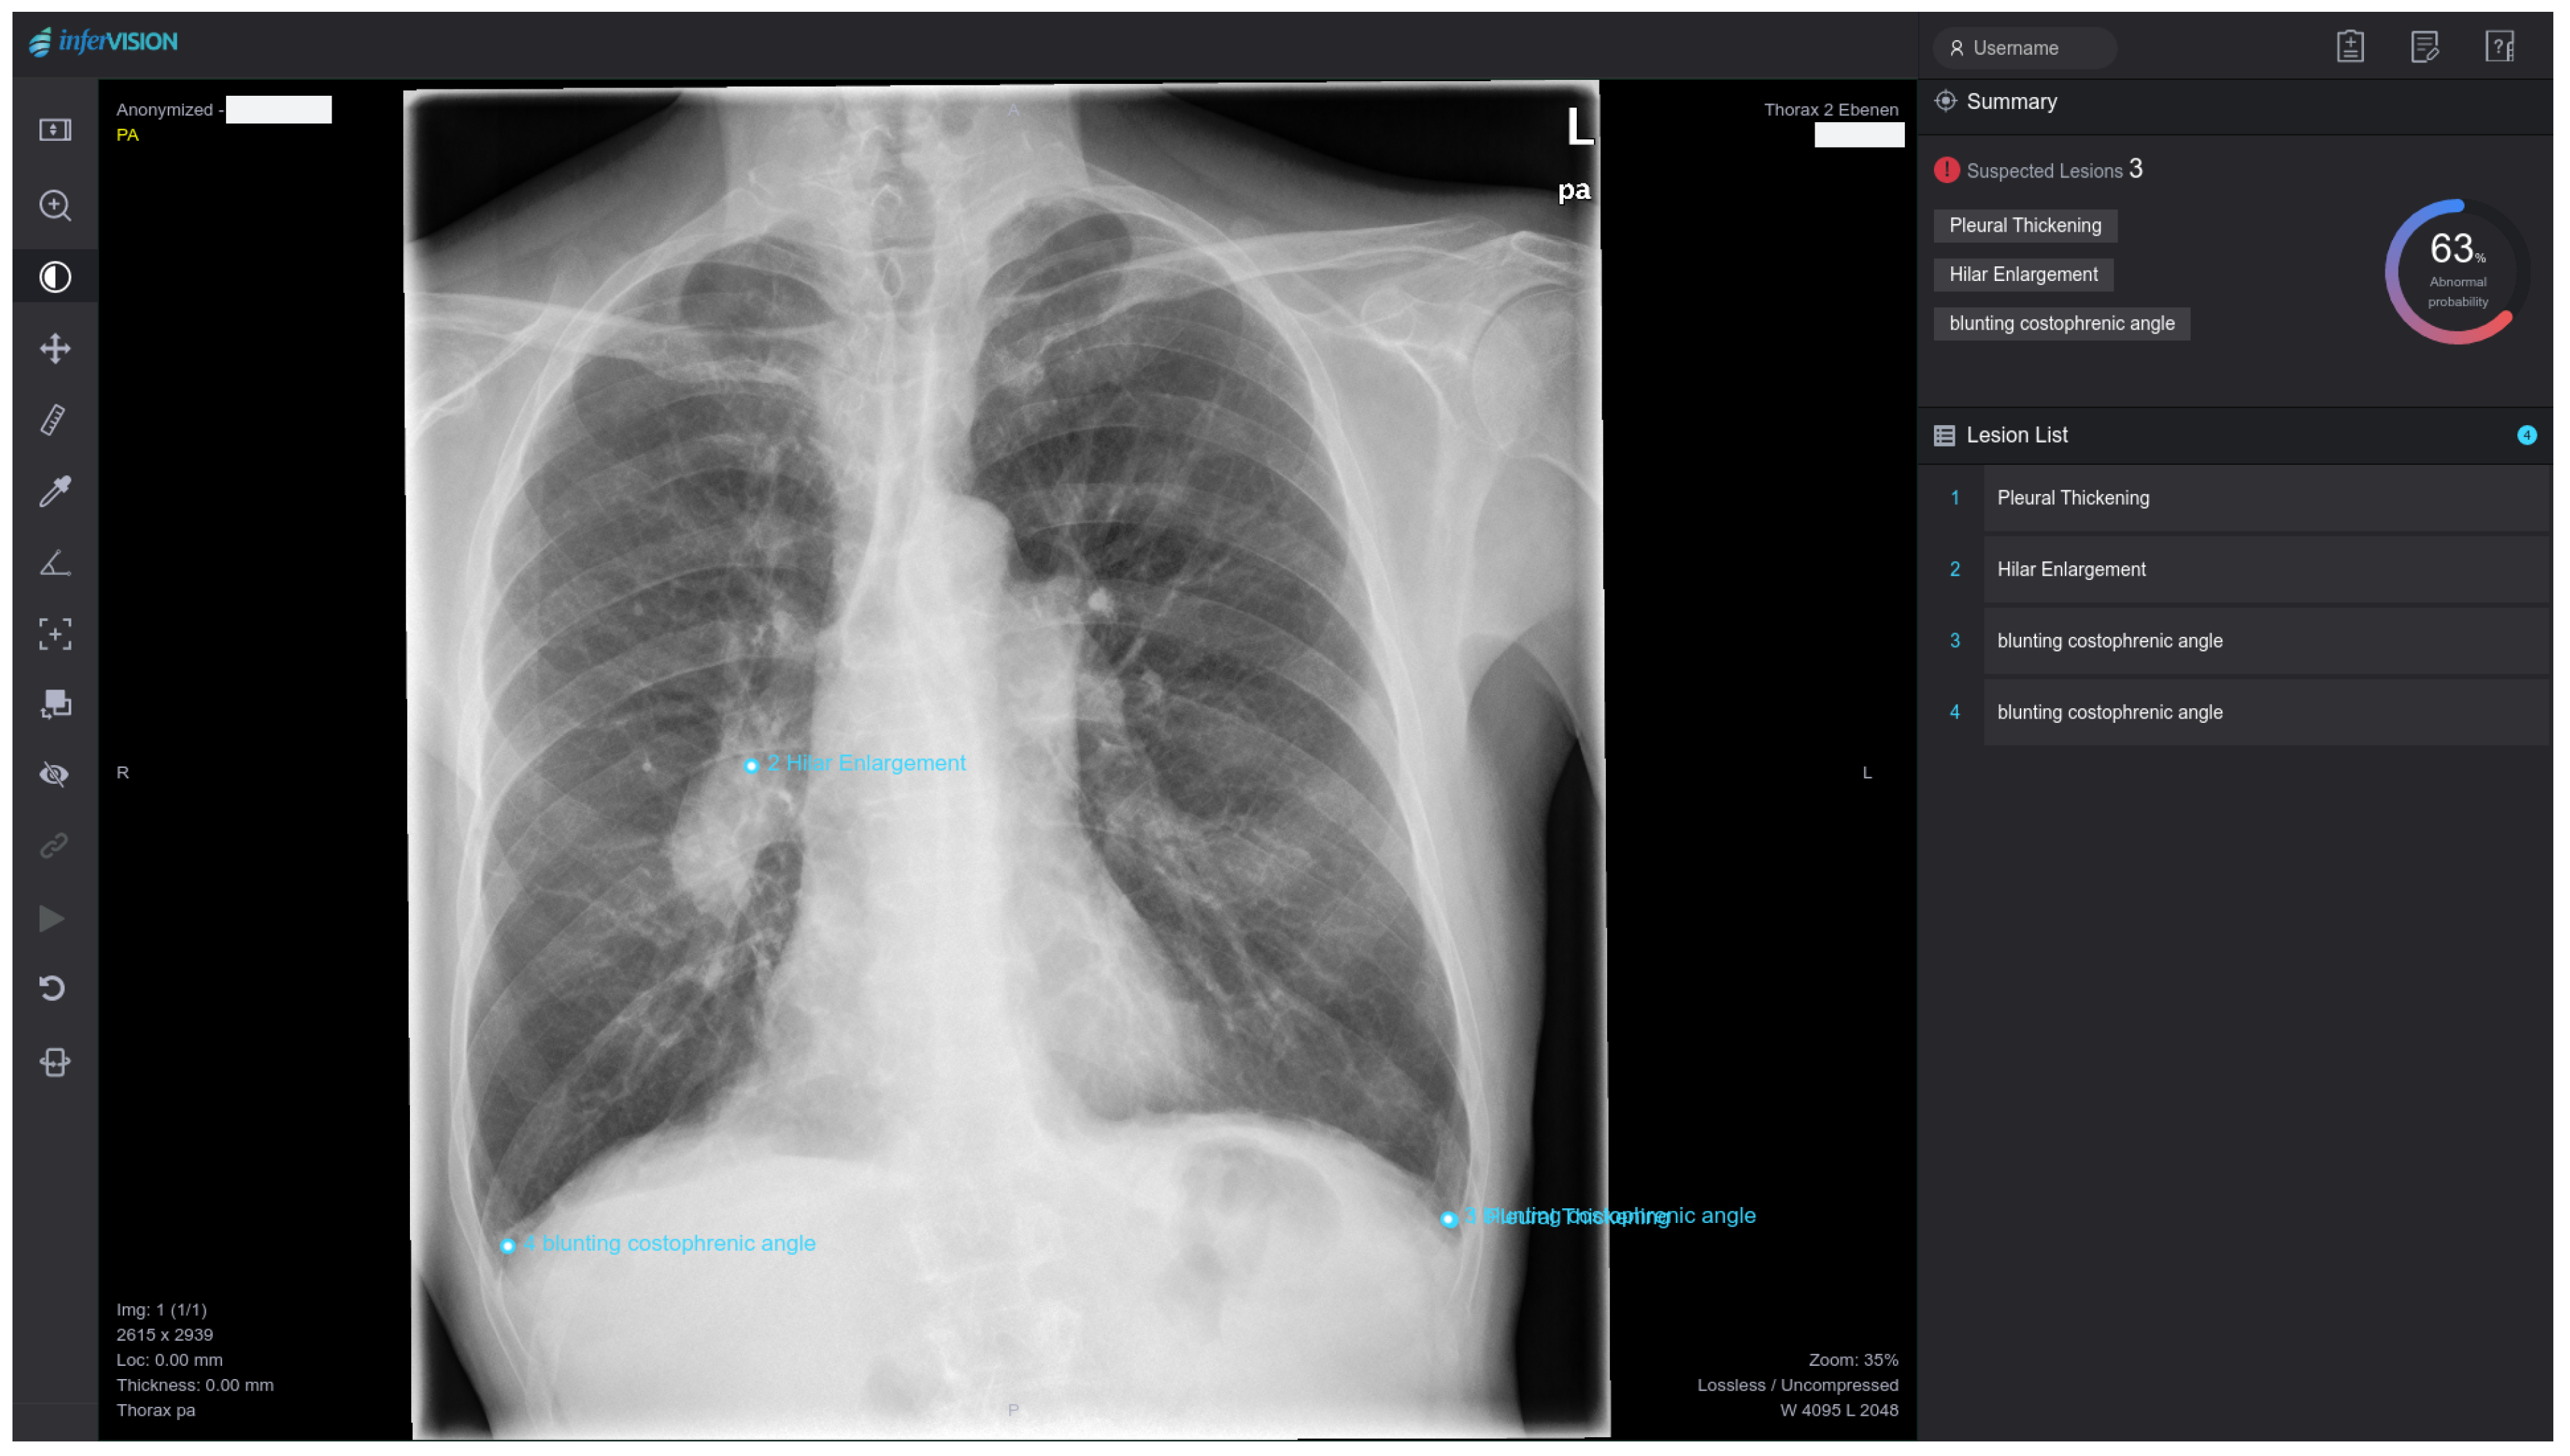

2.3.2. DL Analysis